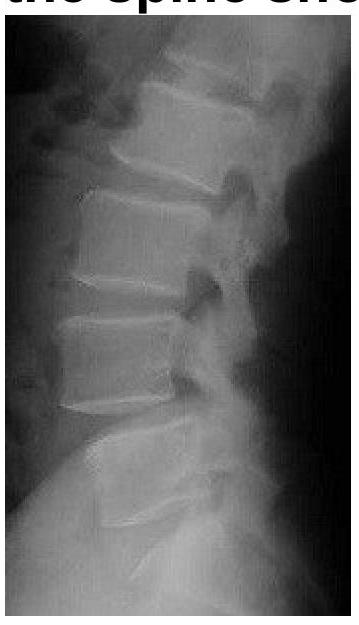

A 35-year-old male presents to the emergency department following a high-speed motor vehicle accident. He complains of severe lower back pain but denies any loss of consciousness or abdominal pain. A lateral X-ray of the lumbar spine is obtained, as shown in the image. The image reveals a horizontal fracture through the vertebral body, extending through the posterior elements. Based on the clinical presentation and imaging findings, what is the most likely diagnosis?

What should be the most likely diagnosis of this 65-year-old lady who presents with backache?

Explanation: ***Chance fracture*** - A **chance fracture** is characterized by a **horizontal fracture** through the entire vertebral body and posterior elements, including the neural arch, typically caused by a **flexion-distraction mechanism** in accidents like those involving seatbelts (lap belt only), consistent with the high-speed motor vehicle accident scenario. - The image distinctly shows a fracture line traversing the vertebral body and extending into the posterior elements, which is the hallmark of this type of injury. *Burst fracture* - A **burst fracture** involves a comminuted fracture of the vertebral body with **retropulsion of bone fragments** into the spinal canal due to axial loading, which is not clearly depicted here. - While it can result from high-impact trauma, the characteristic horizontal disruption of both anterior and posterior segments points away from a solely compressive mechanism. *Compression fracture* - A **compression fracture** primarily involves the **anterior wedging** or collapse of the vertebral body, resulting from only axial compression forces without significant involvement of the posterior elements. - The presented image shows a fracture extending through the posterior elements, which is not typical for a simple compression fracture. *Spondylolisthesis* - **Spondylolisthesis** is the **anterior slippage of one vertebral body over another**, often due to pars interarticularis defects (spondylolysis) or degenerative changes. - This condition involves vertebral displacement, not a fresh fracture line across the body and posterior elements as seen in the image.

Explanation: ***Spondylolisthesis*** - The lateral X-ray image reveals an **anterior displacement of one vertebral body over the one below it**, which is characteristic of spondylolisthesis. - In a 65-year-old lady, degenerative spondylolisthesis due to **arthritic changes and instability** is a common cause of backache. *Osteoporotic fracture* - An osteoporotic fracture would typically show a **compression deformity** or a wedge-shaped vertebral body, which is not clearly depicted here. - While osteoporosis is common in this age group, the primary finding on this image is vertebral slippage, not fracture. *Spondylolysis* - Spondylolysis is a **defect in the pars interarticularis** (a thin segment of bone connecting the superior and inferior articular facets) and is best seen on oblique views or CT. - Although spondylolysis can *lead to* spondylolisthesis, the immediate and most striking finding on this lateral view is the slippage itself. *Discitis* - Discitis, an **inflammation or infection of the intervertebral disc and adjacent vertebrae**, would typically show **loss of disc height** and **endplate irregularities or erosions**. - These features are not the predominant finding on this image, which clearly demonstrates vertebral body displacement.